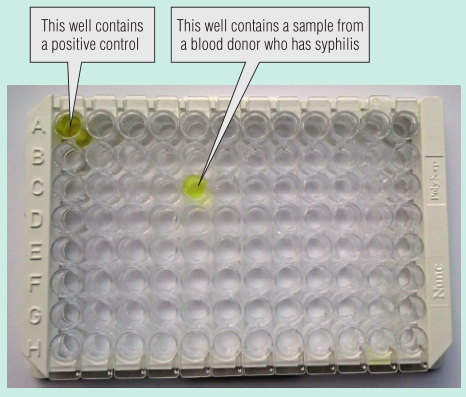

筛查献血者是否患有可能通过血液传播的传染病,筛查的其中一个目的是判断他们是否有感染这些传染病的风险,如果有那么就会被排除。一个例子是男性之间发生性行为,在一些国家这一群体可能因为感染艾滋病毒、梅毒或病毒性肝炎的风险较大而被排除在外。还会进行血液测试,以排除感染风险。这些测试检测在感染或接种疫苗后产生的针对病原体的抗体,就像乙肝病毒一样。

Fig 5.9显示了梅毒的酶联免疫吸附试验(ELISA)筛查试验。ELISA试板包含两个对照孔和94个潜在献血者的样本。第一个孔是用一名梅毒患者的血清进行阳性对照。第二个孔含有从未患过梅毒的人的血清,这是一种阴性对照。这两个控件合并在一起是为了确保测试更加准确。另一个孔显示为黄色,这表明结果是阳性的。

Fig 5.9 检测梅毒的酶联免疫吸附试验(ELISA)试验中用于检测94份血液样本板